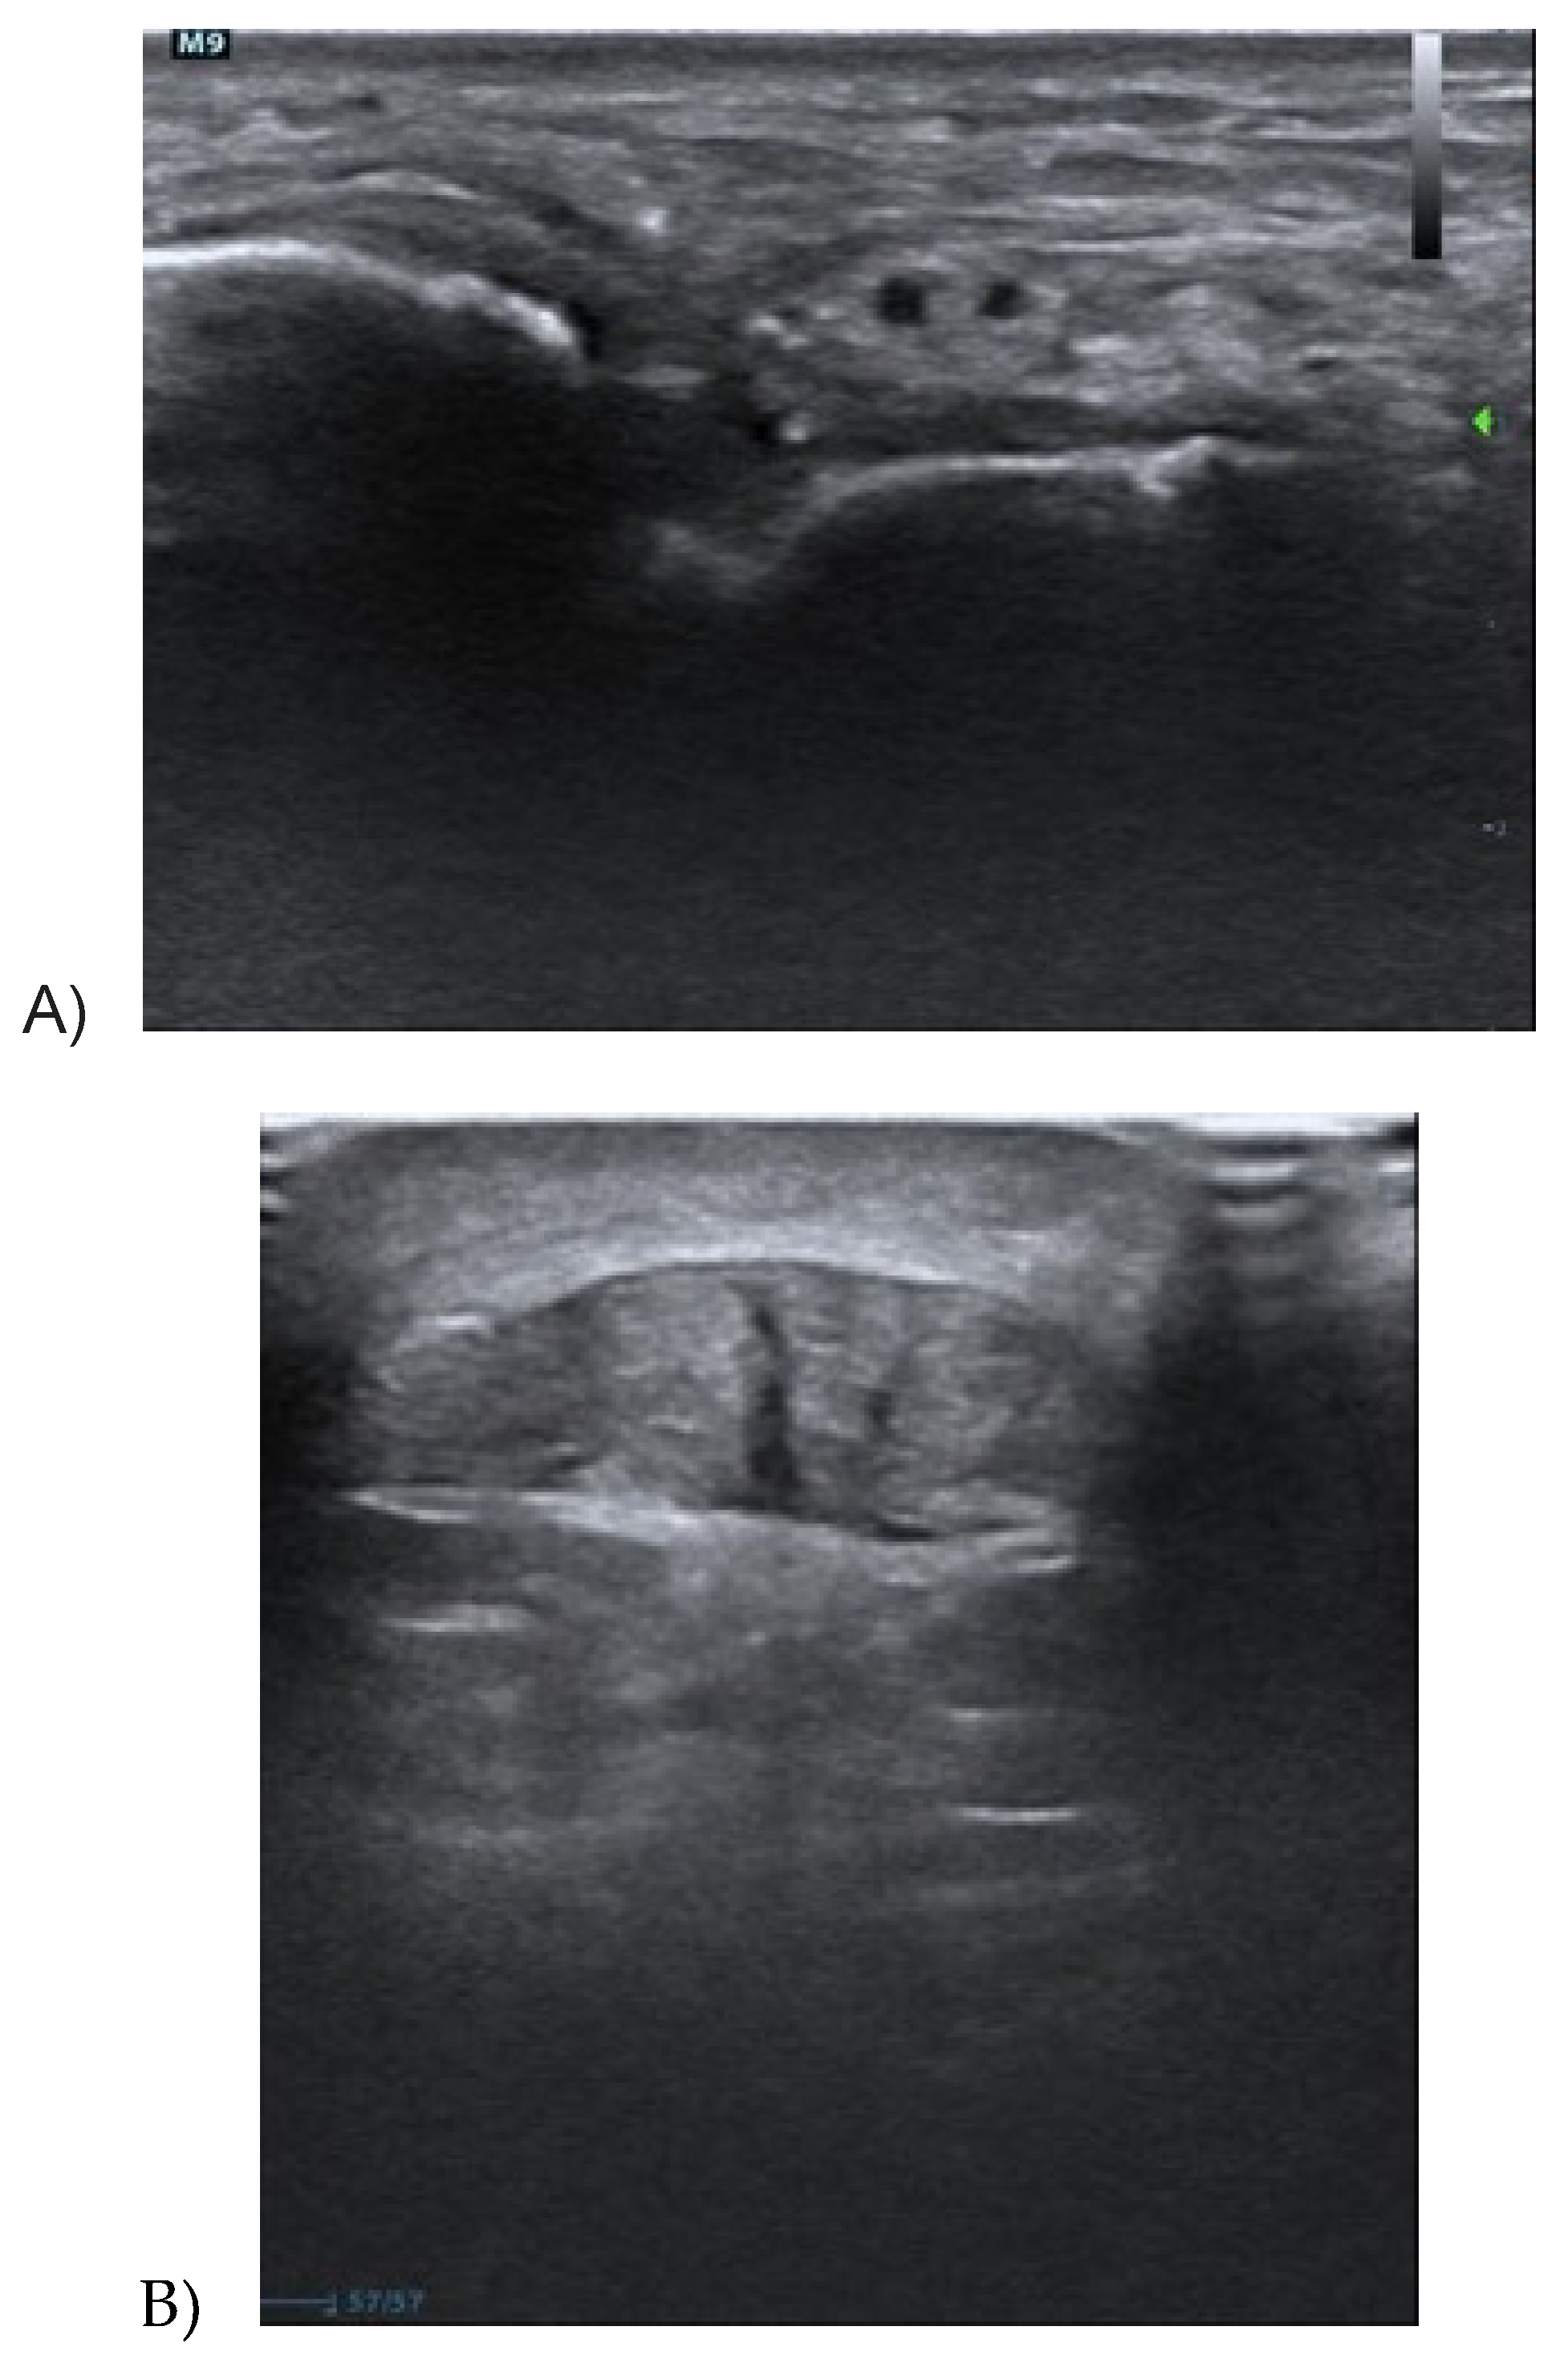

3.1. Achilles Tendinopathy

3.2. Patellar Tendinopathy

3.3. Quadriceps Tendinopathy

3.4. Proximal Hamstring Tendinopathy

3.5. Gluteus Tendinopathy

3.6. Treatments Using Ultrasound Imaging